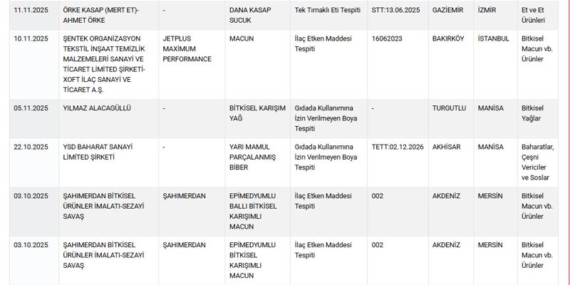

Hastalığın bakteri kaynaklı olması durumunda tedavinin temelini antibiyotikler oluşturuyor. Ancak yanlış ilaç kullanımı, tedavi sürecini zorlaştırabileceği için hastaların mutlaka bir hekim kontrolünde tedavi görmeleri gerekiyor.